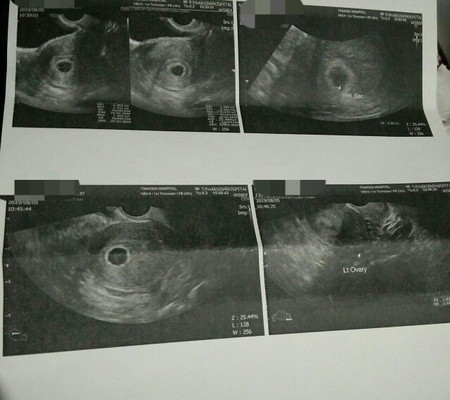

เคยอัลตราซาวด์ตอน 6 week พบถุงการตั้งครรภ์ ภายในถุงการตั้งครรภ์มีถุงไข่แดงอยู่ด้วยเป็นถุงเล็กๆ คุณแม่ไม่ต้องเครียดนะคะอายุครรภ์ยังน้อยอยู่รอสัก 8 week น่าจะเห็นตัวน้องและได้ยินได้เต้นของหัวใจแล้วค่ะ

ของเราก็ซาวครั้งแรกทางหน้าท้องตอน 6 week เห็นแต่ถุงอาหารยังไม่เห็นตัวน้องเหมือนกันค่ะ แต่หมอก็บอกอายุครรภ์ยังน้อย น้องยังตัวเล็กเกินกว่าจะเห็นทางหน้าท้องได้ แต่ที่ซาวดูก็เพื่อให้มั่นใจว่า เราไม่ได้ท้องนอกมดลูก แล้วก็ได้กินยาบำรุงยาวๆไป ซาวอีกทีตอน 8 week เห็นเป็นจุดเล็ก มีหัวใจกระพริบๆ คุณแม่อย่าเพิ่งกังวลนะคะ ทานยาบำรุงอย่าให้ขาด ทำใจให้สบายๆ ไม่มรเลือดออกก็โอเคแล้วค่ะ

Đọc thêmเราค่ะ เจอแต่ถุงตอน 6w หมอนัดไปทุกอาทิตย์ เพราะเราเคยท้องลม ... จนมา วีคที่ 8-9 นี่แหระ เหนตัวอ่อน เปนกลมๆขาวๆ แล้วก้ฟังคลื่นเสียงหัวใจ เราต้องซาวทางช่องคลอด เพราะยังอายุครรภ์น้อย พอได้ 10 w ก็ซาวหน้าท้องค่ะ // ถ้าอายุครรภ์น้อย ซาวหน้าท้องจะยังไม่ค่อยเหนอะไรค่ะ หมอบอก

ซาวตอนเกือบ 6w เจอแต่ถุงตั้งครรภ์คะ หมอนัดอีก 2 อาทิตย์ เพิ่งไปมะวาน เจอตัวน้องและเสียงหัวใจเต้นคะ ใจเย็นๆนะแม่น้องอาจยังเล็กมากคะ

ซาวตอน6w ก็เจอแค่ถุงตั้งครรภ์เหมือนกันจ้า และเจอตัวเด็กตอน 8 w